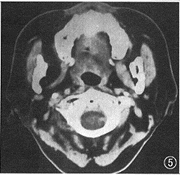

图5 与图4同一病例,右侧翼肌及咬肌萎缩

2.肿瘤CT表现:(1) 大小为1.5 cm×1.0 cm~6.7 cm×6.5 cm;(2) 密度为较密集的小囊状低密度改变组成的筛样结构21例(图1),均匀密度7例,部分筛样、部分均匀密度5例;(3) 形态无定形20例(图2),类圆形11例,长条形与多结节形各1例;(4) 边缘不清晰20例,清晰13例,是由于周围正常脂肪组织环绕对比所引起;(5) 特殊改变:发生在气管的3例中,均表现为肿瘤绕气管腔后壁及两侧壁生长,以后部为主,管腔受压变形,但气管黏膜面仍保持光整(手术证实),甲状腺向两侧推移并均有累及(图3)。腮腺5例,同侧面肌和(或)颊肌呈萎缩改变者3例。发生在腭、鼻腔鼻咽、上颌窦等处肿瘤易侵犯翼腭窝向颅内浸润且合并颅底骨质破坏(5/10),其中侵犯中颅窝卵圆孔3例,表现为卵圆孔扩大或局部骨质破坏,同侧翼肌及咬肌萎缩(图4,5)。本组仅1例作MRI检查,发现肿瘤沿神经侵犯,表现为神经增粗(图6),此改变在CT上无法表现。

3.沿神经生长并侵犯神经:肿瘤容易沿着神经生长,可延伸至距主要瘤块相当长的距离,此改变CT表现有时不明确,而MRI则可比较清楚地反映此特点,表现为神经顺行或逆行增粗[6]。此种改变很少见于其他肿瘤,特征性强。如果肿瘤沿颅神经逆行生长,就易侵犯到颅内,并侵犯该神经(图7),引起神经症状(疼痛、麻木感)或相应神经支配的肌肉萎缩,从而间接显示神经受侵的改变,肿瘤侵犯颅神经提示预后不良[2]。